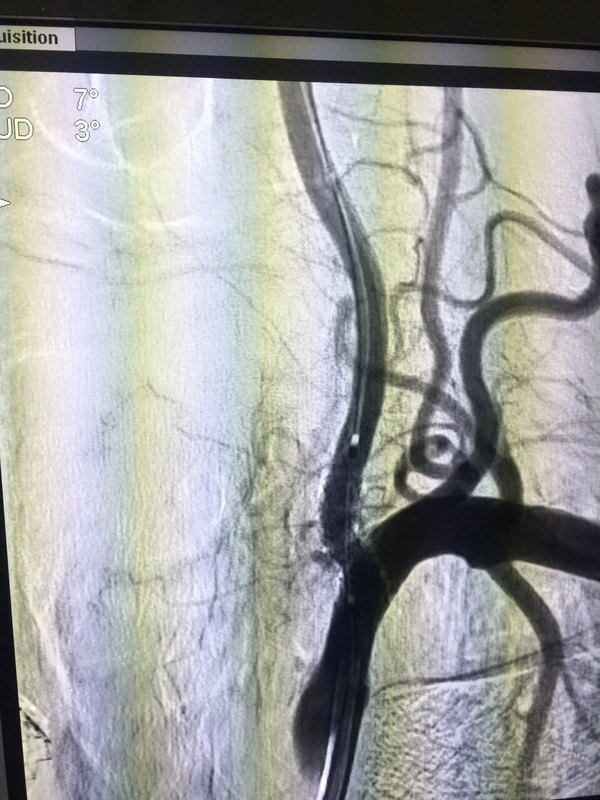

頭暈很常見,但有的頭暈卻是致命性昏迷的前兆,特別是頭暈伴有肢體麻木等情況,老年人合并有高血壓、糖尿病等情況的更應(yīng)特別重視。 下面一個病例:72歲,老年男性,反復(fù)眩暈1月余,檢查發(fā)現(xiàn)椎動脈開口狹窄,導(dǎo)致基底動脈缺血,腦干小腦缺血,頭暈行走不穩(wěn),予以支架植入,狹窄解除。 腦動脈支架植入,從根本上治療腦血管病。腦動脈支架植入安全可靠,使越來越多的患者獲益。出現(xiàn)頭暈?zāi)垦?,一定要警惕腦血管病,一旦腦血管閉塞,將造成嚴(yán)重的后果。殘疾或者死亡!危害嚴(yán)重。